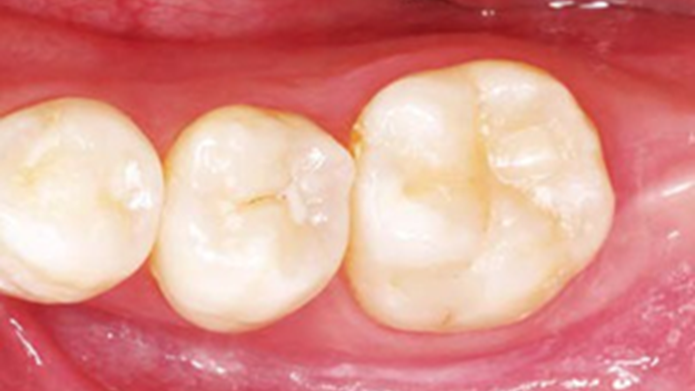

Clinical case: Single molar implant with bone augmentation

- Courtesy of Dr. Jung Sam Lee, Korea -

Keywords

AnyOne, bone augmentation, osteotomy socket, peri-implant tissue, autogenous bone, GBR, single replacement, Auto-Max, Dr. Jung Sam Lee

Products:

AnyOne implant system, Auto-Max